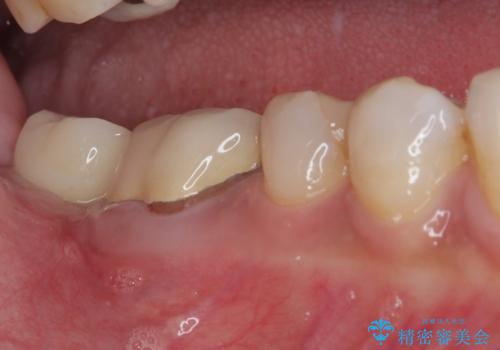

放置した奥歯 部分矯正を併用したインプラント補綴治療

- 右下欠損部のインプラント治療を希望して来院された患者様です。

右下の欠損部を長期間欠損を放置していたことで、咬み合う上の奥歯が動いてしまっていたので、まずは上顎奥歯の部分矯正を行うこととしました。

理想的な咬み合わせに改善した上で、インプラント補綴治療を行うこととしました。

部分矯正を行ったこと治療期間は長くなりましたが、違和感のない咬み合わせを達成することができました。